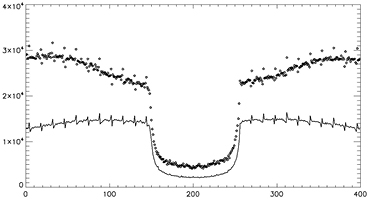

From figure 4, one can observe a noisier 202 keV sinogram when compared to the 307 keV sinogram. A study was performed to see if the transmission data was contaminated by the emission data and if the contamination is a function of emission source activity. 3 uniform phantoms (20 cm diameter × 26 cm in height) with varying activity from no activity to 0.5 mCi and 2.2 mCi were placed in the geometric center of the PET field of view. These phantoms were measured for 1 h and rebinned into the 2 transmission trues sinograms (prompts – delays). A profile across all the sinogram elements with summing over 100 angles and summing of all axial planes are shown in figure 5 for 202 and 307 keV transmission sinograms.

Figure 5. Profiles of the 307 keV (left) and the 202 keV sinograms. Profile is across all elements and sum of 100 angles and sum of all axial planes. No activity (-), 0.5 mCi (*) and 2.2 mCi (◊).

Standard image High-resolution imageThere is some contamination in the 307 keV transmission data around the edge of the object which can be seen as a small mismatch between the profiles. The 202 keV transmission data has more visible contamination from emission data. The tails of the sinogram increases in events further away from the center of the field of view. This may be a result of when the backscattering angle approaches 90° and the energies are close to equal to each other and both events fall into the 202 keV window. The change of the profiles in the region outside the objects boundaries in the cold phantom when compared to the region outside the object in the 307 keV profiles could be a result of the 307 keV photons scattering in the object into the 202 keV energy window.

A thought to make the 202 keV data usable is to model the 511 keV backscatter events and correct for these events in the collected data or add information to the 202 keV blank collection sinogram. This would recover the events that are discarded when emission activity is present in the scanner's field of view. It also creates a new transmission type flux that adds to the Lu-176 flux that's presented here. The model would require some information on the emission flux and the emission volume's attenuation information. Both of these pieces of information are available from the current technique using only the 307 keV transmission data. Since it was shown that the 307 keV transmission data is mostly uncontaminated by emission data, the attenuation maps produced from this data can be used for the initial emission reconstruction. Using the emission distribution, a model of the backscattering of 511 keV photons can be performed to correct for the increase of counts not accounted for in the blank scan. This would allow for the removal of the condition where if the first event is in the 202 keV energy window, the second event cannot be in the 307 keV window. Figure 12 illustrates the additional information that can be acquired by not applying the backscatter condition to the 202 keV transmission data. The figure is a re-plot of figure 5 with 2.2 uCi and a cold 20 cm uniform phantom in the center of the field of view. It is seen that the addition of the backscattered events almost doubles the amount of events in the 202 keV transmission data. This increase of information is dependent on the amount of activity that illuminates the detectors.

Figure 12. Profile of 202 keV sinograms plotted the same as figure 5. The sinograms of the cold phantom (–) and the 2.2 mCi phantom (◊) were acquired and rebinned without the discrimination of backscattered events.